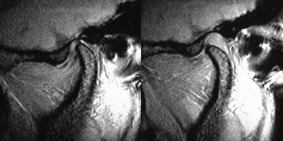

滑走運動をスムーズに行うためには関節結節と下顎頭の間に位置する関節円板が下顎頭とともに協調して動く必要があります。右のMRI(左:開口時、右:閉口時)では前方に滑走した下顎頭と関節結節の間にやや黒っぽく細長い部分として関節円板が見られます。(画像にマウスを合わせてください。下顎頭と関節窩(黄色の概形線)の間にある関節円板(赤の概形線)が下顎頭ともに前方へ移動しているのが確認していただけます)

(関節円板は軟組織ですのでレントゲンには写りません。MRIは水分子に振動を与え、その動きを捕らえて画像化したものですので、軟組織も見ることができます。骨の表面は水分が少ないので黒く写ります。)